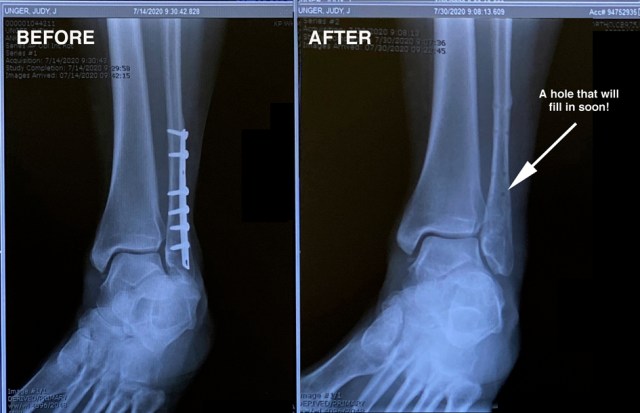

The miracle of healing is clearly visible in these two pictures. In only five weeks my scar is now almost invisible.

This picture displays the seven-inch plate and screws that were given back to me – my memento from hardware removal surgery on July 17, 2020.